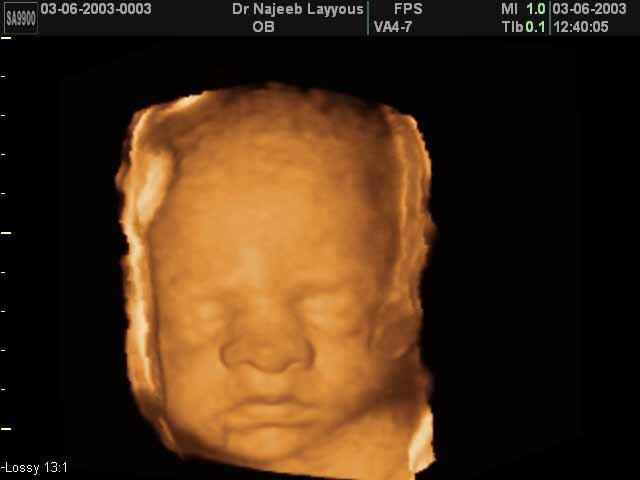

- صور لوجه الجنين في داخل الرحم

صور لوجه الجنين بجهاز الالتراساوند ثلاثي الأبعاد | الدكتور نجيب ليوس